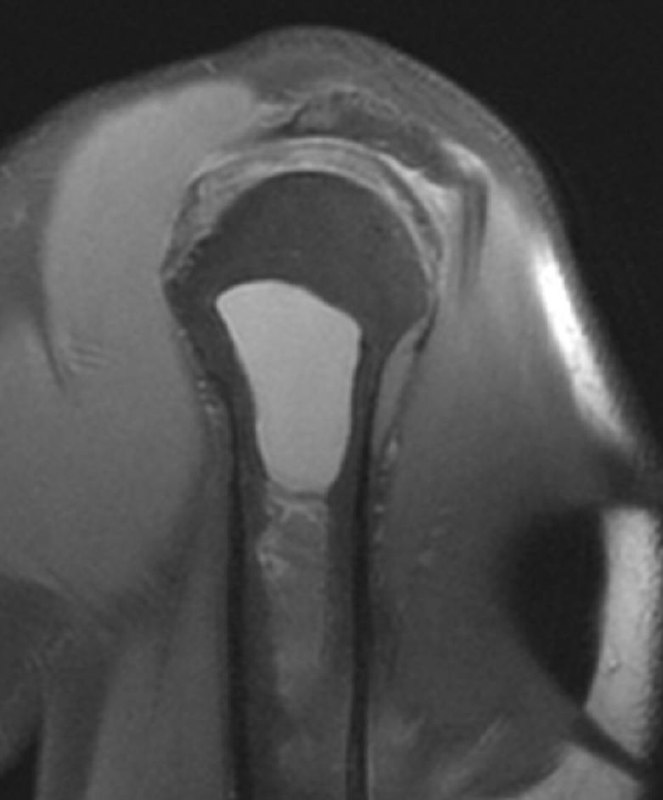

показательный случай острого (хорошо, свежего!) разрыва сухожилия длинной головки бицепса плеча, с приличным диастазом. стрелками указаны края дистального и проксимального фрагментов сухожилия. На последнем снимке - пустая межбугорковая борозда